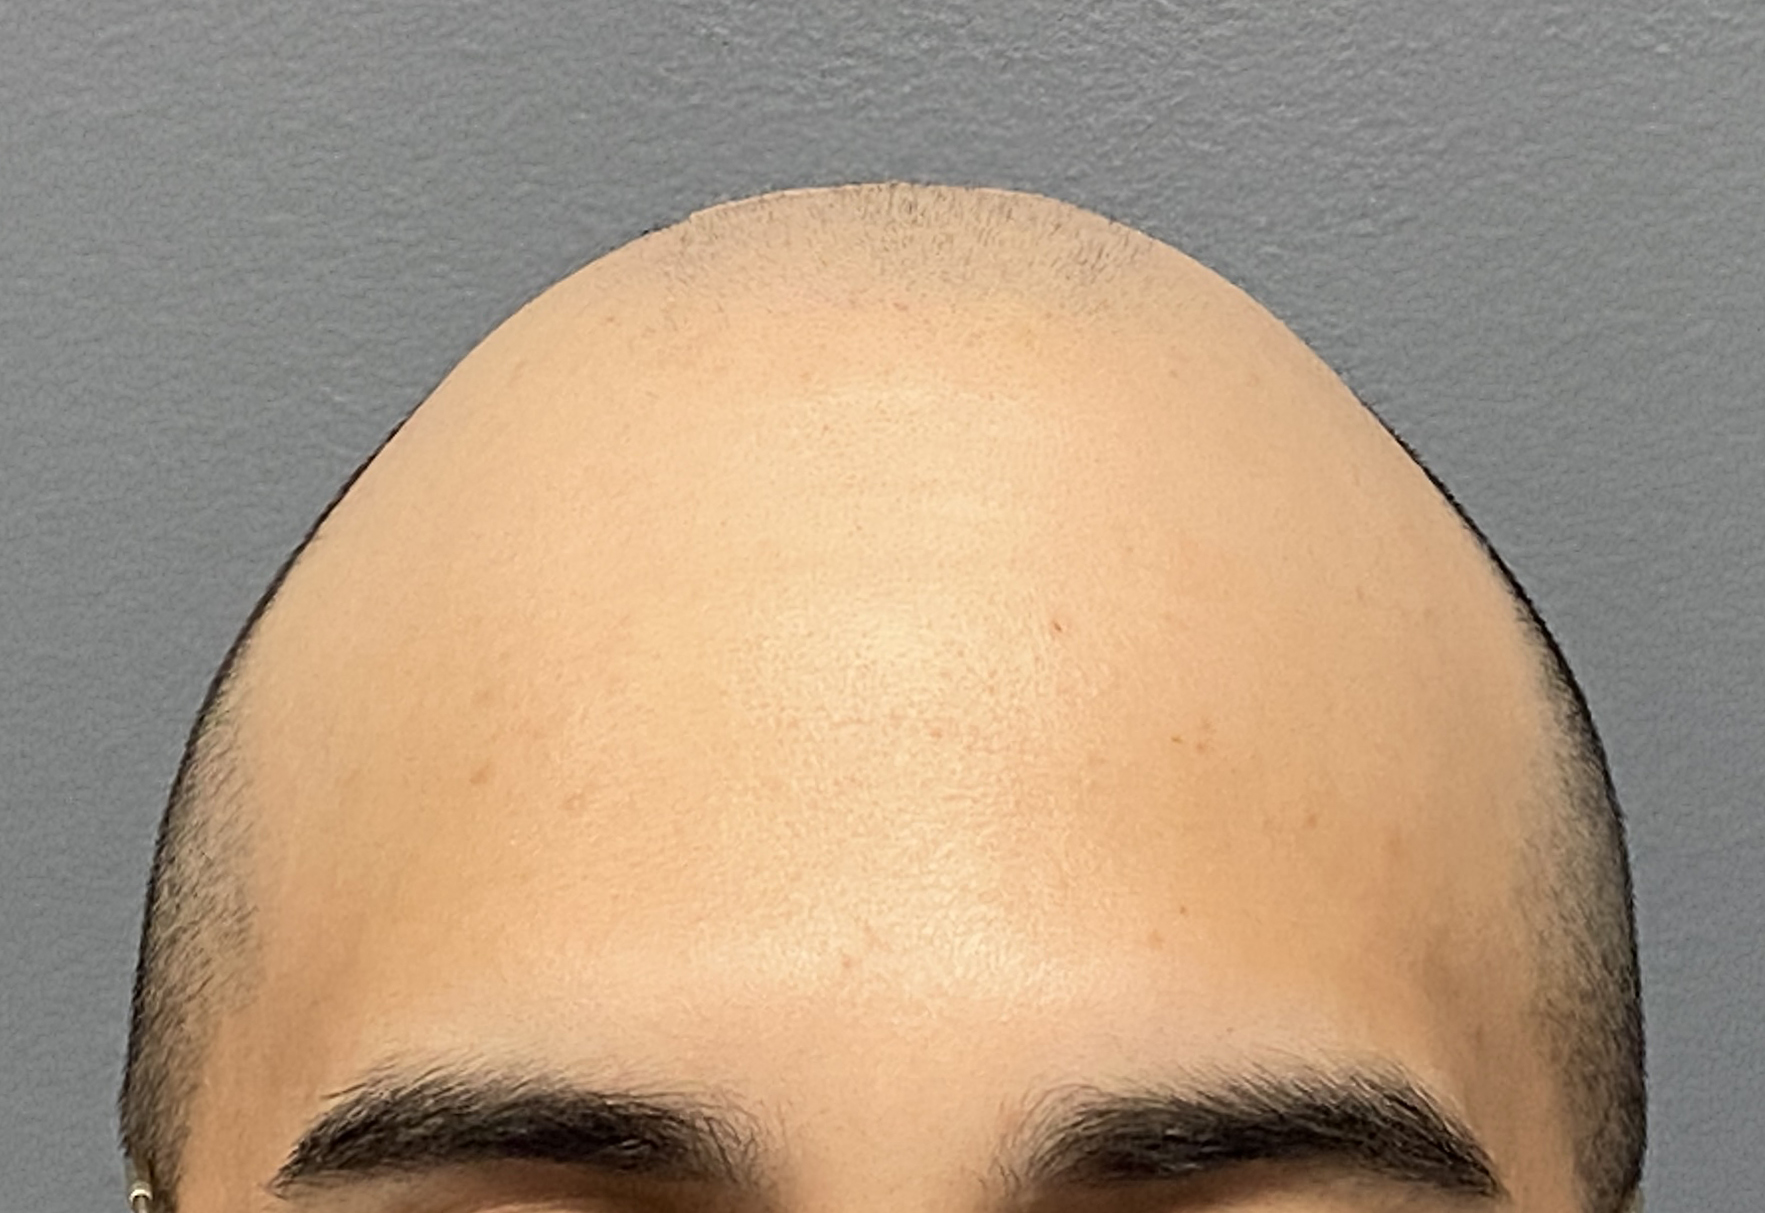

Desire for reshaping of an asymmetric flat back of the head in a shaved head male.

A combined back of the head reshaping procedure was done with a custom skull implant, sagittal ridge reduction and a right temporal muscle reduction.

Desire for reshaping of an asymmetric flat back of the head in a shaved head male.

A combined back of the head reshaping procedure was done with a custom skull implant, sagittal ridge reduction and a right temporal muscle reduction.